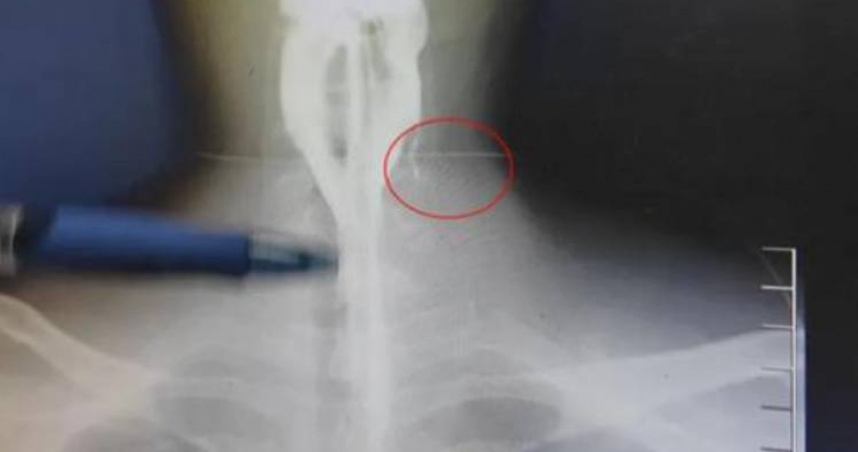

醫生表示,「我們對患者進行碘水造影,大部分的造影劑在患者吞咽的時候,都會從咽喉到食道到患者胃里面去,然而他左側的頸部也有一點造影劑的顯影,說明這個位置有個瘺口跟竇道,患者可能患有梨狀窩瘺。」

鄢敏說明,胎兒發育時,咽喉與頸部組織未能完全分離,在咽部梨狀窩(喉嚨兩側凹陷處)與頸部之間形成異常瘺管,就是梨狀窩瘺。這條細長的竇道像一條暗渠,一端開口於咽喉,另一端可延伸至頸部深層組織,成為細菌和異物入侵的「秘密通道」。

醫生指出,這條通道特別愛開在左側頸部,占患者中的90%,可能與胚胎期鰓弓發育不對稱有關。鄢敏說,阿偉膿包裡的瓜子,就是順著這條先天的通道走偏了位置,在脖子「安營紮寨」。不過,阿偉最近沒有嗑過瓜子,他苦苦思索才想到,20年前的夏天,脖子同個位置也發生過類似腫痛,但是吃藥後就好了。